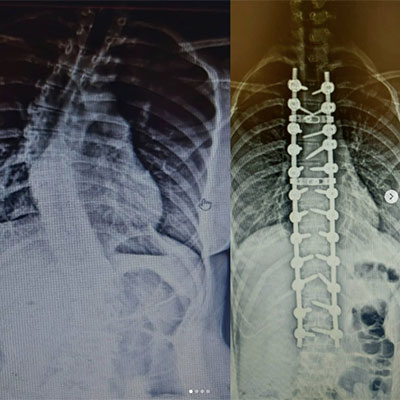

İşlem Görüntüleri

Skolyoz, omurganın yandan bakıldığında S veya C şeklinde eğrilik gösterdiği bir omurga hastalığıdır. Genellikle çocukluk ve ergenlik döneminde başlayan bu durum, omurganın düzgün hizalanmasını engeller. Skolyozun nedeni tam olarak bilinmese de, çevresel, genetik veya nöromüsküler faktörlerle ilişkili olabileceği düşünülmektedir. Hafif vakalardan ciddiye kadar değişen şiddette görülebilir ve bazı durumlarda belirti vermeden ilerleyebilir. Ancak ilerleyen vakalarda, omurga eğriliği ve eşlik eden postür bozukluğu nedeniyle fiziksel rahatsızlıklara, sırt ve bel ağrısına, solunum güçlüklerine ve organlara baskıya neden olabilir. Erken teşhis ve tedavi, skolyozun ilerlemesini engellemeye ve yaşam kalitesini artırmaya yardımcı olabilir.

Omurganın ön ve arkadan bakıldığında 8 - 10 derece üzerindeki sağ veya sol tarafa olan eğriliği ile buna eşlik eden, kendi ekseni etrafındaki dönme hareketinin (rotasyon ) oluşturduğu bir şekil bozukluğudur. Skolyoz omurga deformiteleri içerisinde en sık karşılaştığımız ve ilerleyen evrelerde ciddi duruş bozukluklarına neden olan üç boyutlu bir omurga deformitesidir.